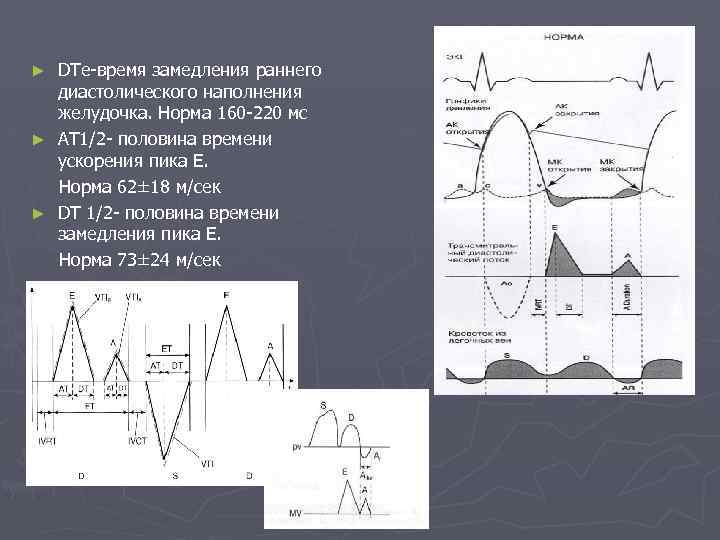

DTe-время замедления раннего диастолического наполнения желудочка. Норма 160 -220 мс ► AT 1/2 - половина времени ускорения пика Е. Норма 62± 18 м/сек ► DT 1/2 - половина времени замедления пика Е. Норма 73± 24 м/сек ►